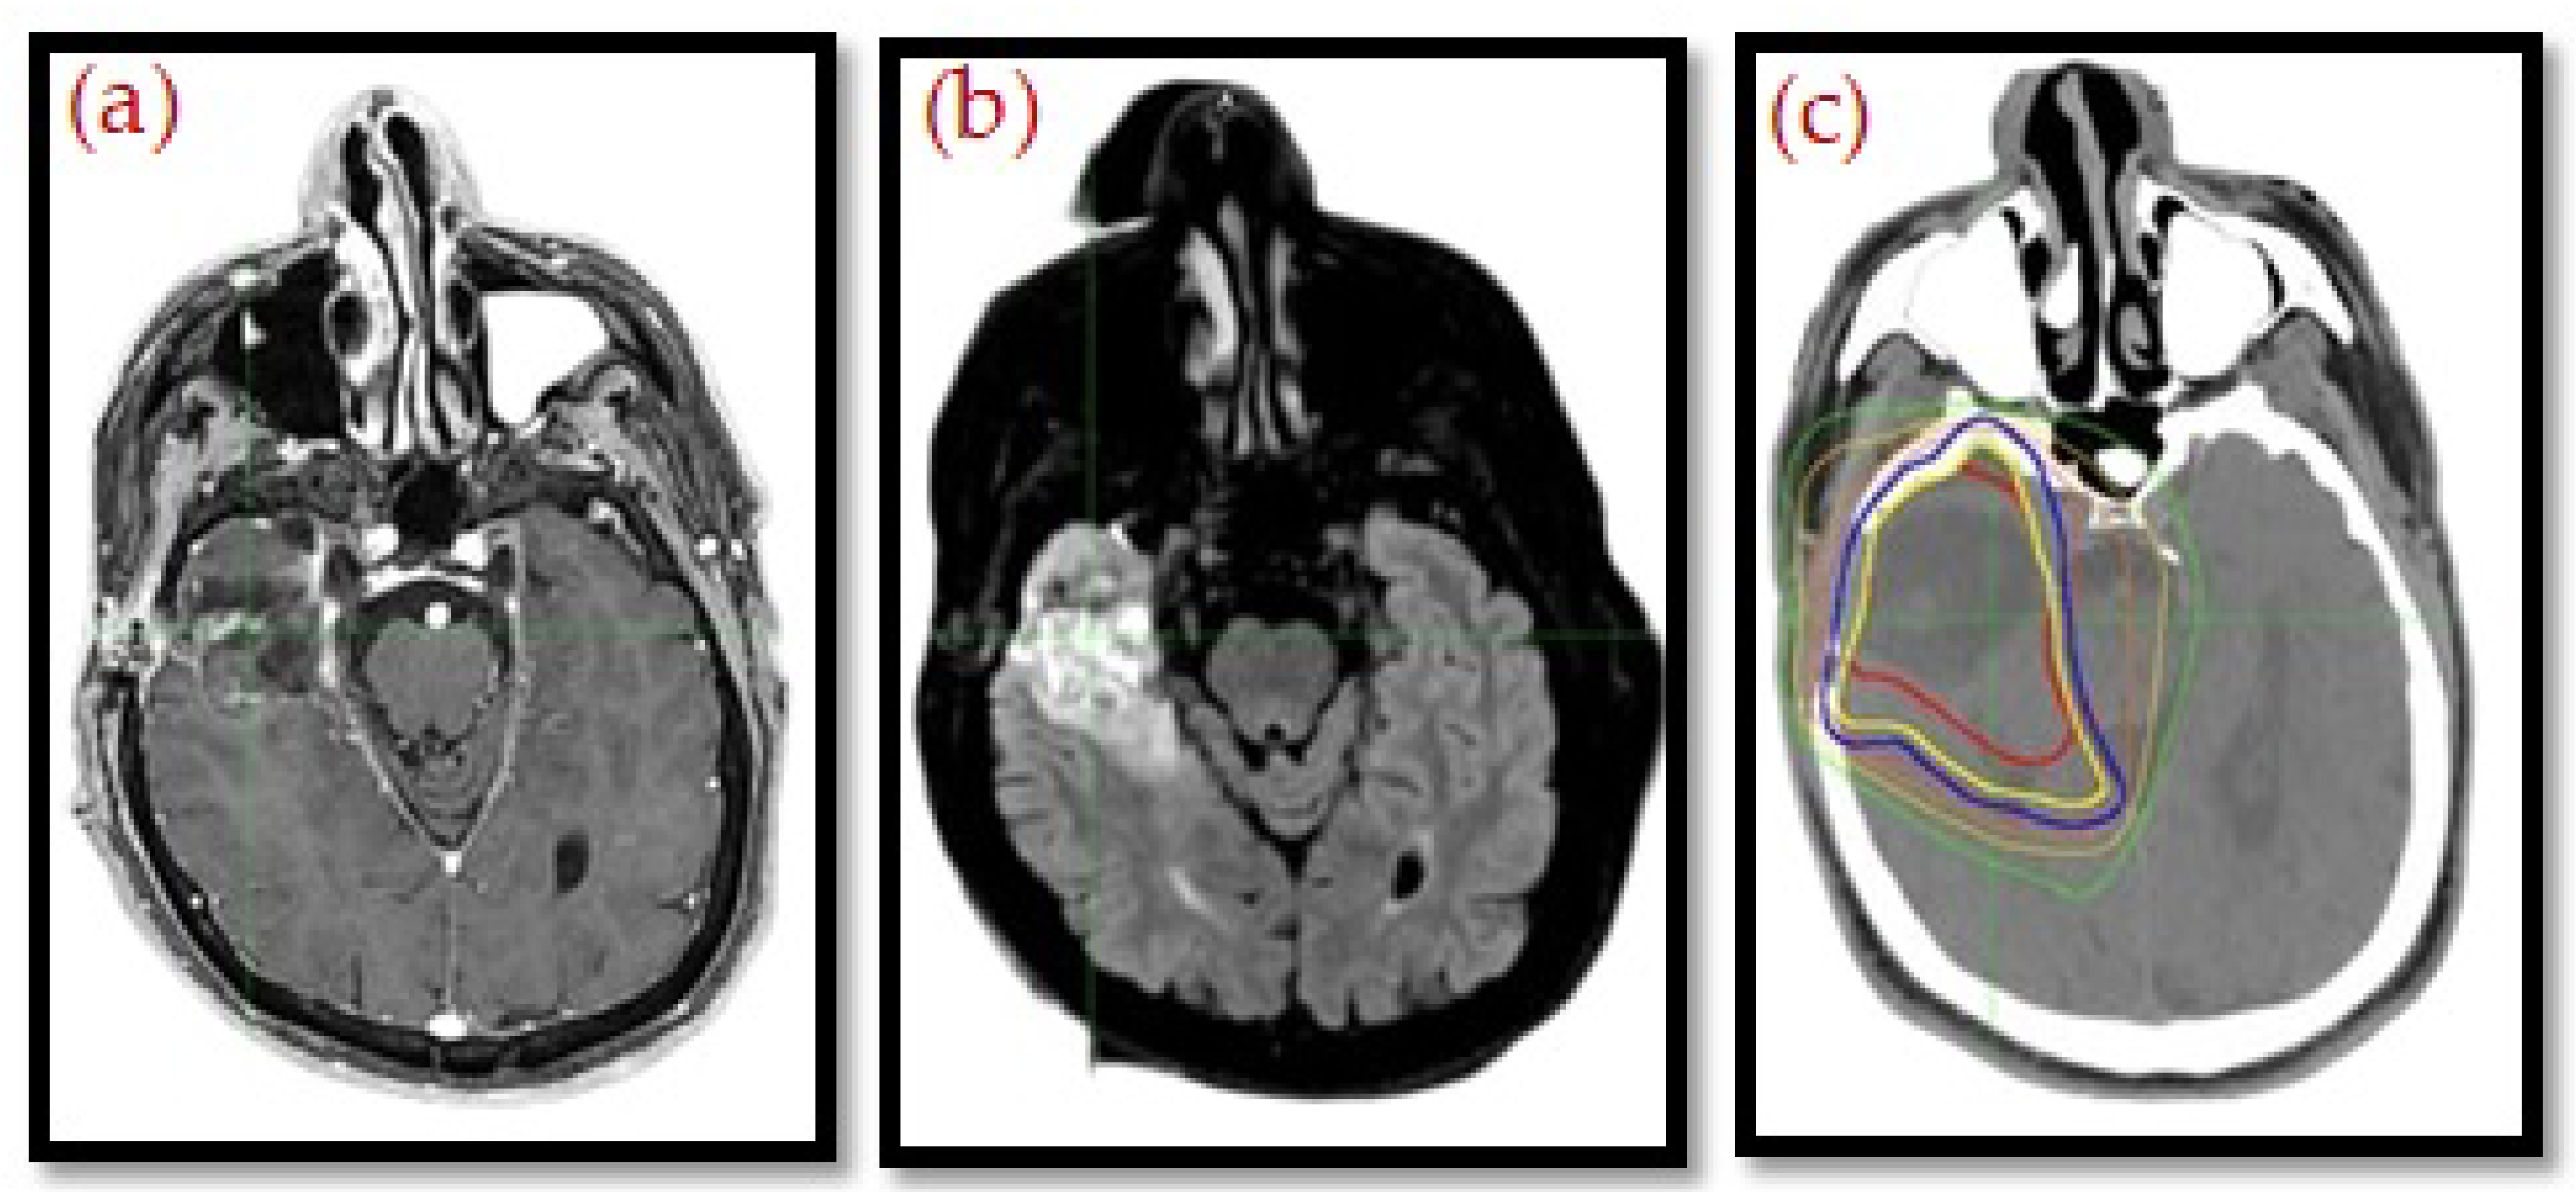

MRI integration is also at the heart of adaptive radiotherapy. MR-Linac systems provide real-time visualization during treatment so that on-table plan adjustments can be made according to daily anatomical changes, as presented in Figure 2 and Figure 3. This feature improves personalization and accuracy and, quite possibly, therapeutic outcomes, and it reduces toxicity. The geometric distortion, protocol standardization, and integration of CT-based dose calculations are also important. Nevertheless, MRI is creating a new paradigm in “head to toe” radiotherapy planning, with increasing evidence supporting its function in precision oncology [20,21,22].

Figure 2. Contrast-enhanced T1w (a) and FLAIR-weighted (b) images, obtained after surgery of a lesion consistent with a glioblastoma, demonstrate the surgical cavity with peripheral signal abnormality, which is included in the distribution of doses for the centering CT (c) [19]. The colored lines represent dose distribution of OAR.